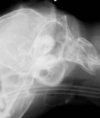

Q

Skull fractures radiographically.

Fracture line must be differentiated from suture line. Fractures are not usually symmetrical.

Image has dark line around midline that is not symmetrical = fracture.